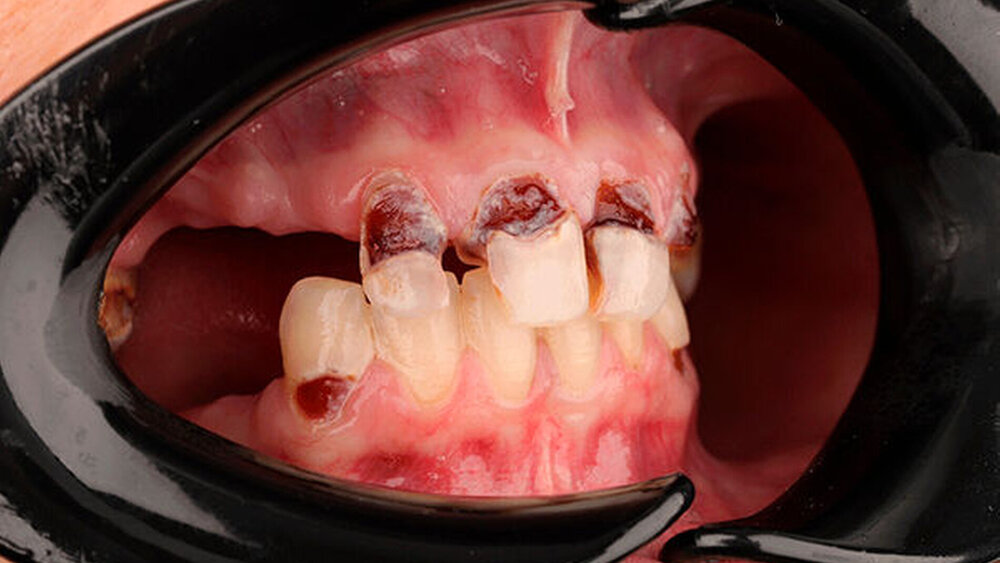

Als die 25-jährige Andrea erstmalig die Praxis konsultierte, litt sie bereits seit mehreren Jahren an starken Beschwerden. Grund für ihre Situation sind zwei Krankheitsbilder, die einerseits isoliert und andererseits im Zusammenspiel schwerwiegende Folgen hatten. Die junge Frau leidet an einer angeborenen genetischen Veränderung, deren Symptom unter anderem eine schwache Zahnschmelzentwicklung ist.

Zudem ist die Patientin an Fibromyalgie erkrankt, einer chronischen Schmerzerkrankung mit einem hohen symptombezogenen subjektiven Leidensdruck. Eine Folge der Erkrankung war, dass sich die Patientin in den vergangenen Jahren durchschnittlich drei- bis viermal pro Tag erbrochen hat. Die daraus resultierende Säureerosion hat ihr ohnehin schon gefährdetes Gebiss erheblich geschädigt.